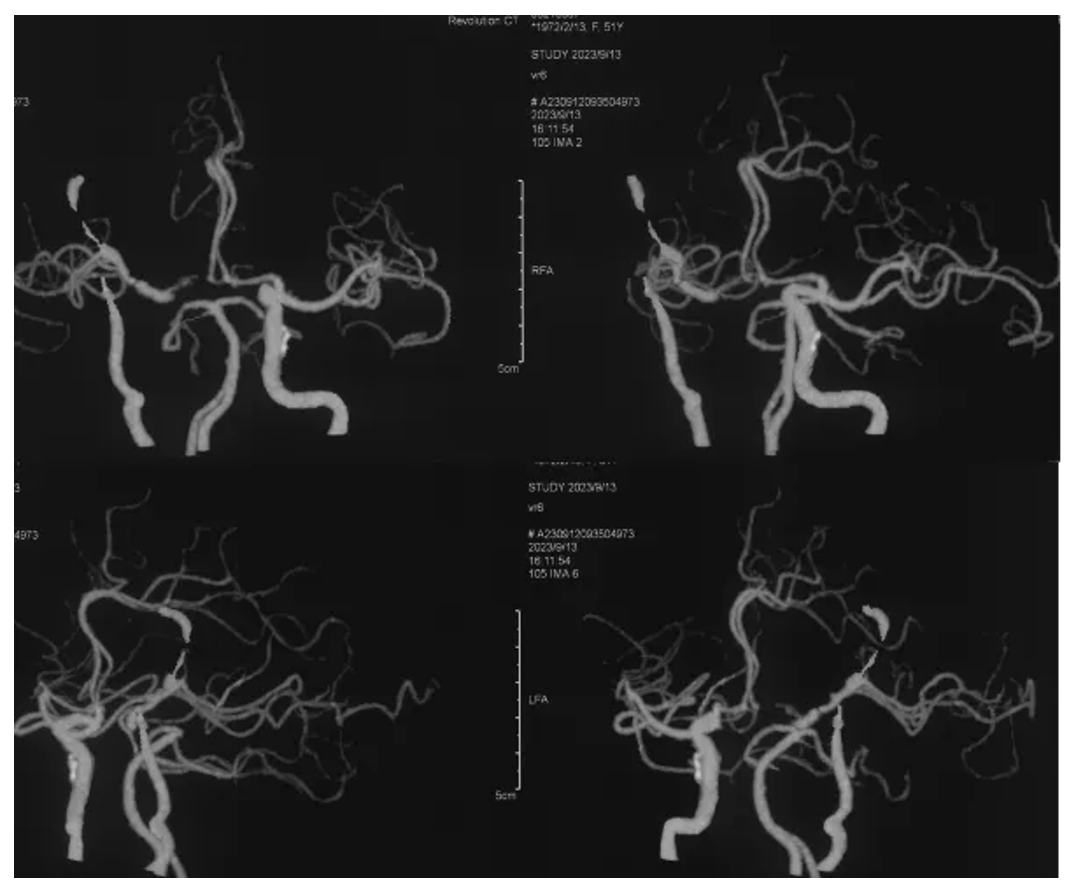

Postoperative MRI enhancement: Showing a major resection of the tumor

Postoperative CTA

Bridging vascular patency